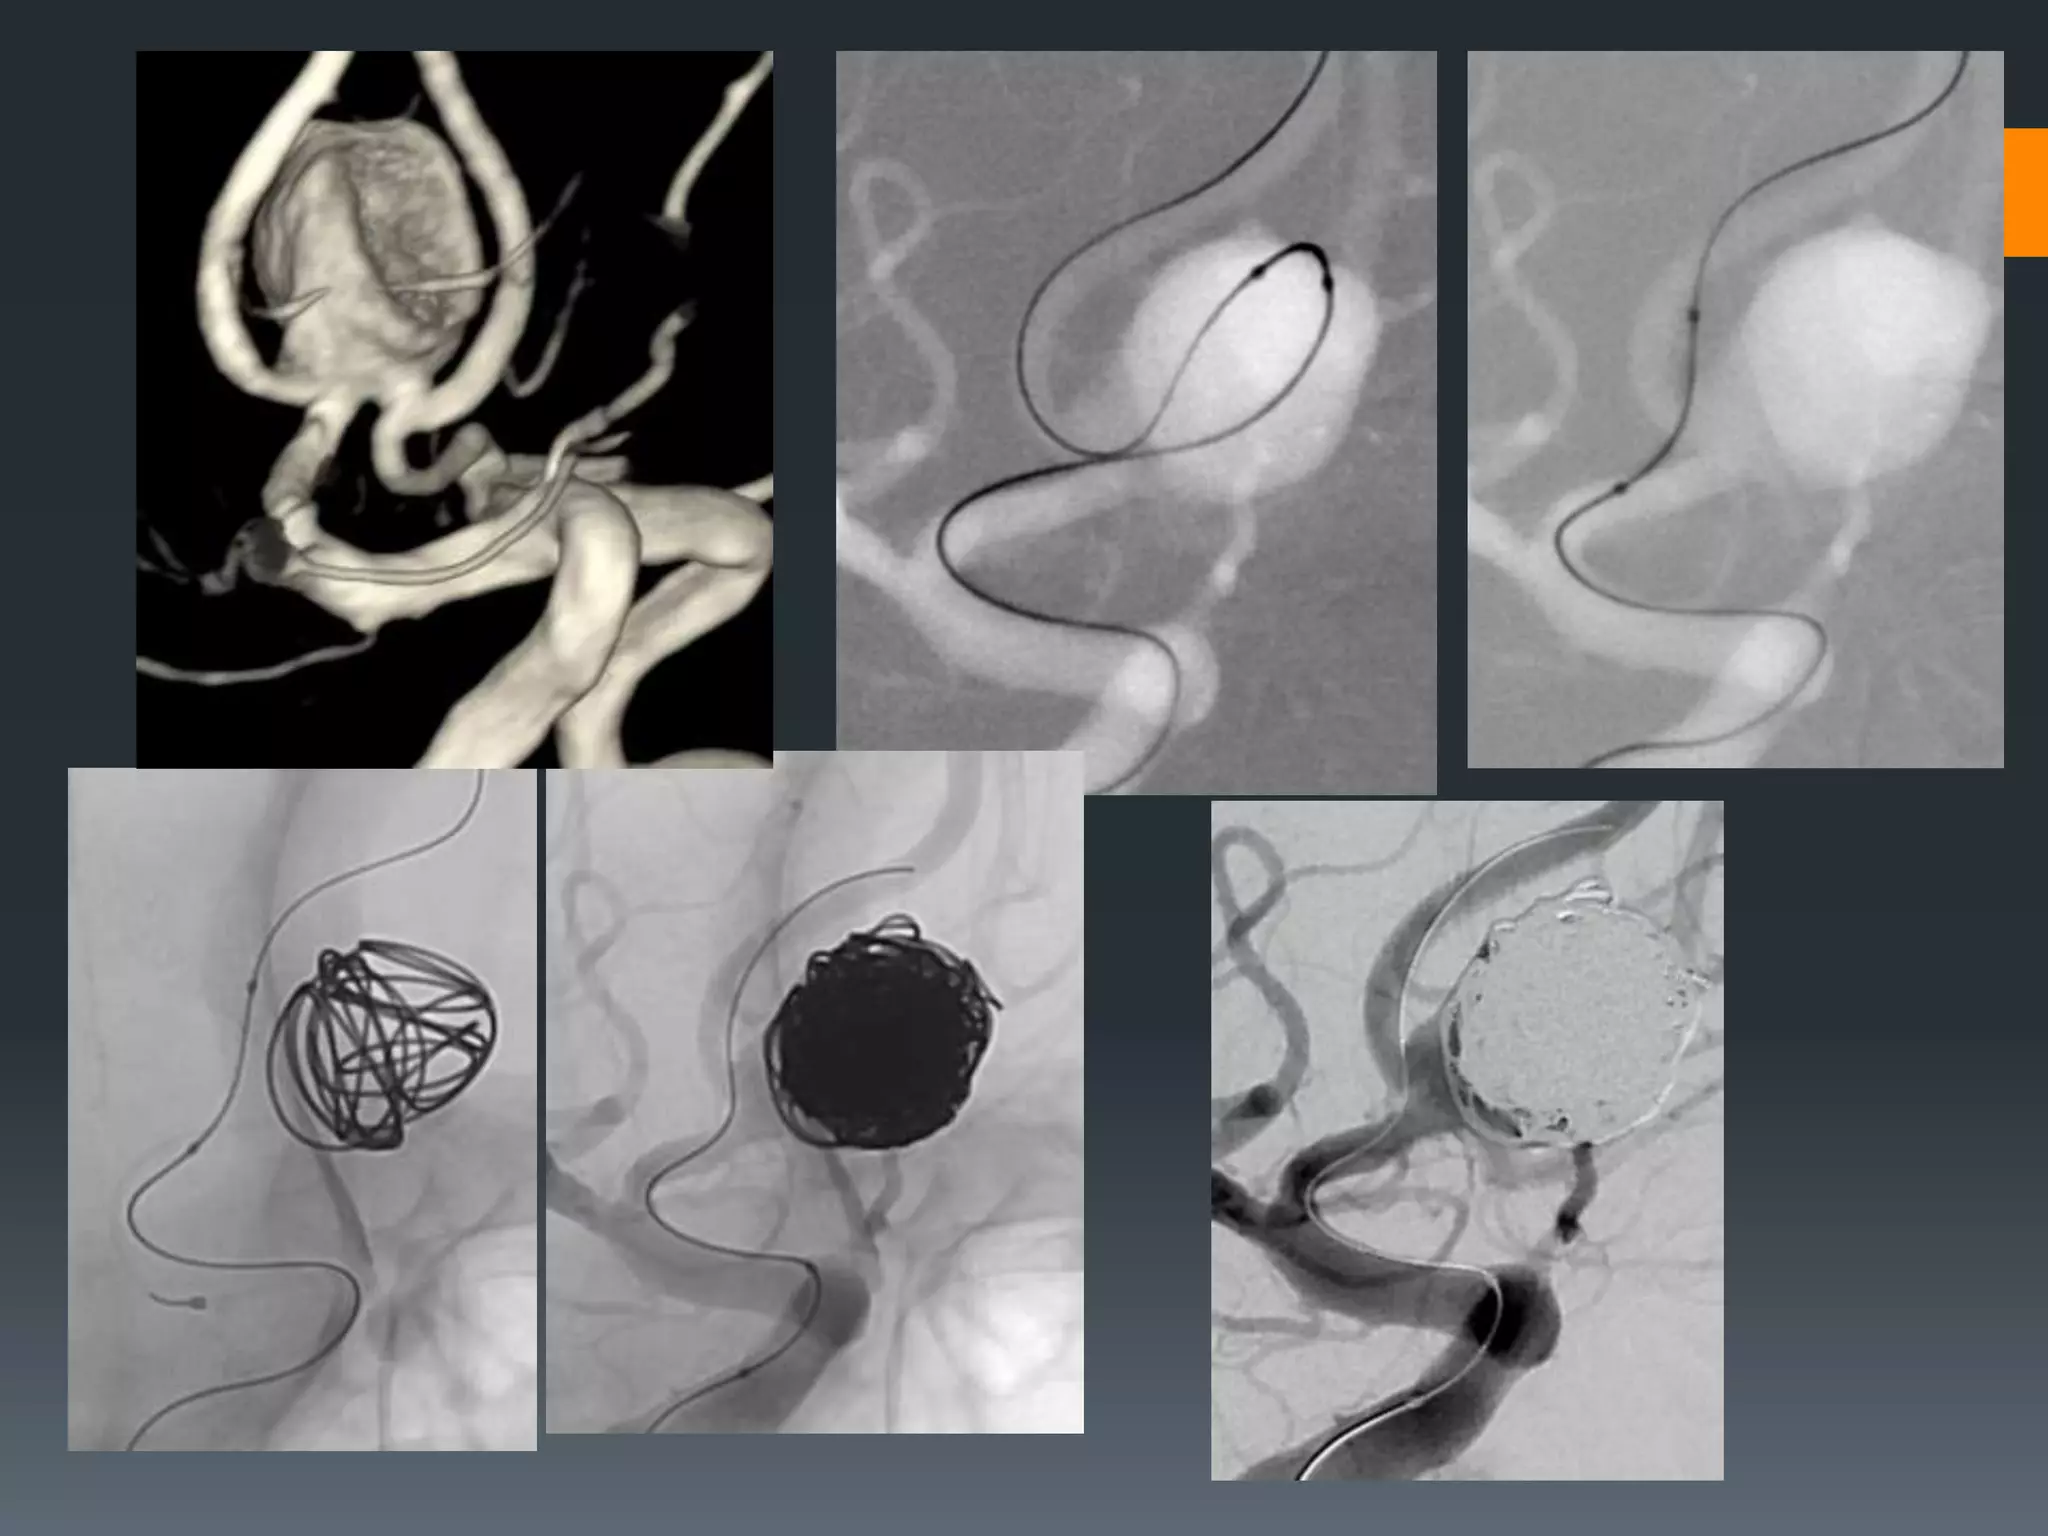

This document discusses tricks and techniques for difficult cannulations during neurointerventional procedures. It outlines strategies for accessing the aortic arch, internal carotid artery (ICA), and areas distal to aneurysms. Long sheaths, distal access catheters, and co-axial techniques are presented as options that have improved cannulation success. Guidance on sheath and catheter selection is provided for different vessel paths. The importance of catheter placement as high as possible in the ICA is emphasized. Reverse curve cannulations are also mentioned. Overall, the document stresses that careful cannulation is critical for procedural success and different strategies may be needed depending on the vessel target.